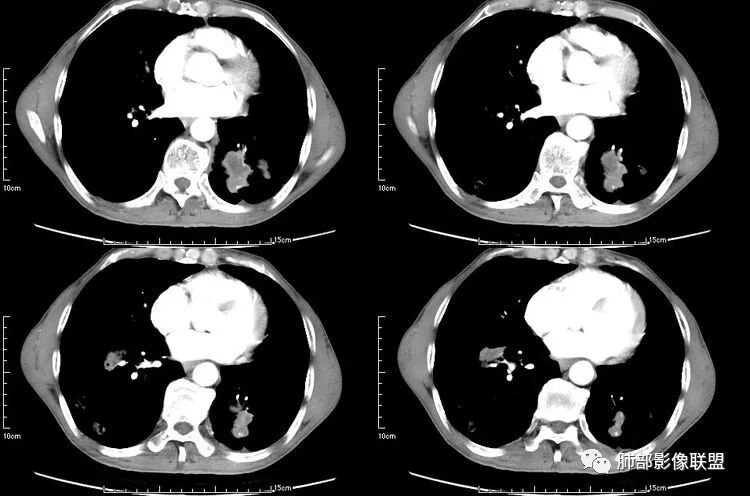

患者老年男性,咳嗽、咳痰、痰中带血伴胸闷2月余。长期大量吸烟史。查肝肾功能、血糖、血脂、心肌酶、电解质、血沉、C反应蛋白、抗“O”、类风湿因子、抗核抗体谱无明显异常。肿瘤标志物提示NSE、CYFRA21-1稍升高。胸部CT:肺气肿背景,左肺下叶后基底段不规则肿块影,见支气管截断,内见大片状低密度区及部分血管影,增强轻度强化,远端空洞形成。双肺多发不规则实性结节影、见毛刺、胸膜牵拉及血管集束,结节内见空洞形成,部分可见血管影,多位于胸膜下。双肺见多发肺大泡。综合考虑左下肺恶性病变并双肺转移。鳞癌或淋巴瘤可能。鉴别血管炎性病变及真菌感染。

本病例左肺下叶肿块,有深分叶、毛刺、胸膜牵拉凹陷、支气管截断及纵隔内淋巴结肿大等征象,都均支持病灶为恶性,如腺癌,而且叶间裂的多发结节也提示是腺癌来源可能大;双肺多发结节、肿块,大部分病灶有分叶、毛刺及胸膜凹陷的恶性征象,与原发肿瘤本身的性质有关,所以应该与左肺下叶肿块同源,而且双肺多发病灶内空洞也具有多样性;

此病例中空洞形态多样,内壁不光整,有分隔影,周围未见明显卫星灶及钙化灶,结核不太符合;患者病史慢性病史,无明显发热,缺乏中毒临床表现,急性感染基本排除;各种中性粒细胞胞浆抗体阴性,没有鼻窦炎,肾脏等病史,基本排除血管炎;霉菌性空洞常见于免疫机能低下者, 常为空洞、肺炎、伴“ 晕圈”征的结节及支气管扩张合并存在。